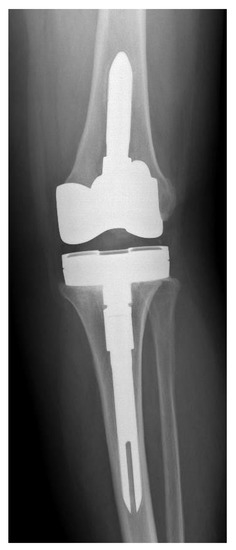

Figure 1. Preoperative X-ray of knee joint with Streptococcus anginosus infection of patient number 5.

The cost for treating these 18 patients using 1-stage revision, according to the cost criteria described by Srivastava et al. [17], totaled USD 435,186 (18 patients × USD 24,177 per patient). Added to this cost are the costs of the six surgical complications occurring in five patients: two acute debridements (USD 17,723 per patient = USD 35,446), one aseptic revision (USD 24,177 per patient), one tendon repair (USD 24,177 per patient), one closed reduction (USD 24,177 per patient) (Figure 1 and Figure 2), and one neuroma excision (USD 24,177 per patient). The total cost for treating these 18 patients using a 1-stage revision amounted to USD 567,340. If these patients had been treated using 2-stage revision, the costs would have totaled USD 858,492 (18 patients × USD 47,694 per patient) without any complications. Therefore, the total economic savings for our hospital for these 18 patients was USD 291,152.